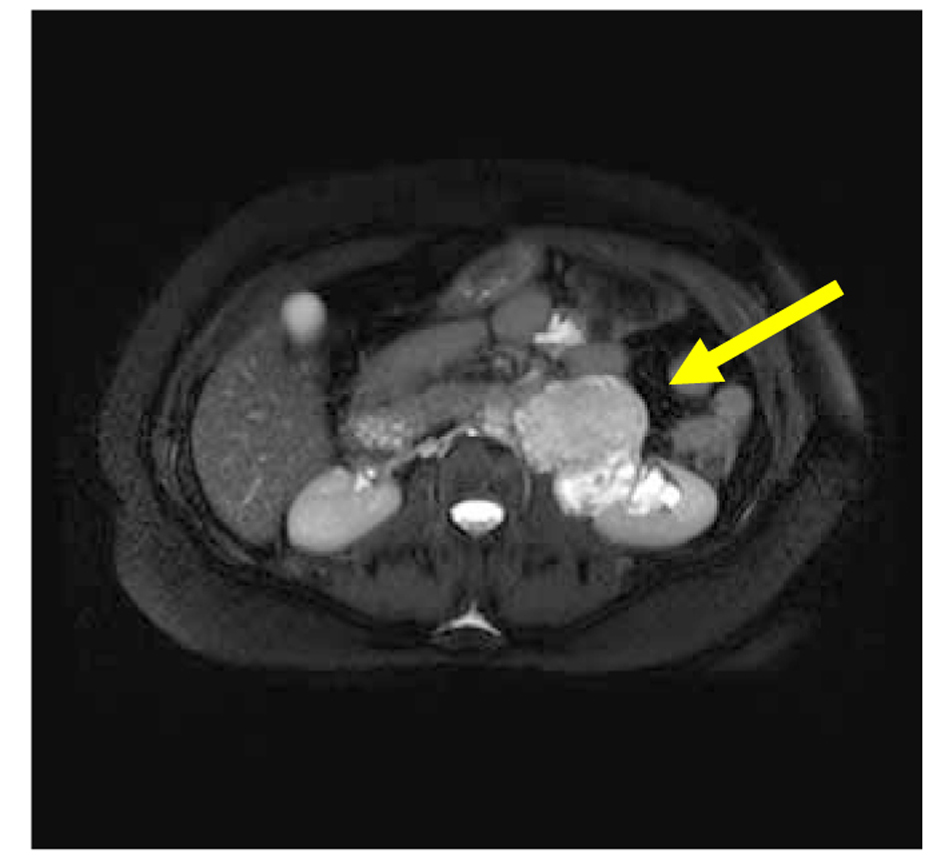

A 51 years old man presented with flank pain and nausea being present over the last 4 months. The biochemical analyses were as follows: AST and ALT normal, FBG: 123 mg/dL; TSH: 0.713 mIU/mL, creatinine: 0.75 mg/dL, urea 26 mg/dL, hemoglobin 13.3 g/dL, WBC: 4,100/mm3, hematocrit: 38.7%, platelets: 230,000/mm3. Physical examination was unremarkable. Medical history of the patient revealed hypertension, diabetes mellitus and hypothyroidism. Renal ultrasound (US) examination revealed hyperechogenic solid mass which was 70 × 58 × 66 mm in size on the left renal pelvis. On MRI examination, grade II hydronephrosis was found on the left kidney and a mass lesion of 78 × 58 × 68 mm was found on the renal hilus which was hypointense on the T1-weighted images and hyperintense on the T2-weighted images and invading the renal pelvis (Fig. 1, 2). Apparent contrast enhancement was observed. The surrenal gland was normal in appearance. There was no lymph node on the para-aortic area. The patient underwent left transperitoneal radical nephrectomy.

![]() Click for large image | Figure 2. Magnetic resonance imaging: mass in pelvis renalis of left kidney (arrow), the axial shows. |